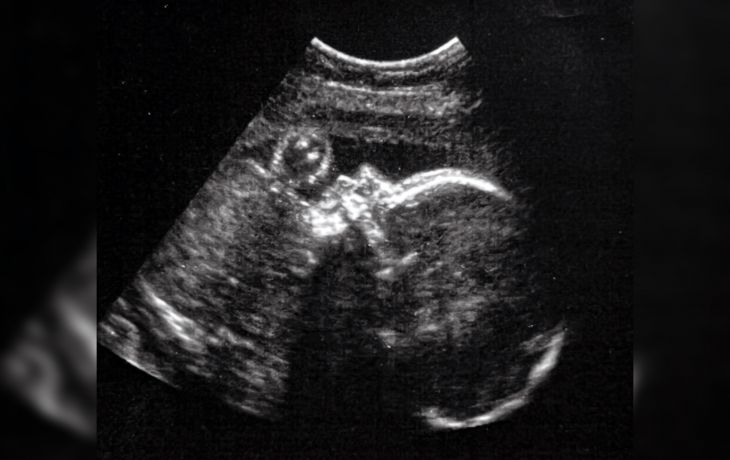

Médicos del Boston Children's Hospital y del Brigham and Women's Hospital, de Estados Unidos, realizaron con éxito una cirugía inédita: corrigieron desde el útero una malformación vascular potencialmente mortal en el cerebro de un feto.

El equipo médico corrigió una malformación conocida como vena de Galeno, la cual produce insuficiencia cardíaca, lesión cerebral grave e incluso representa riesgo de muerte poco después del nacimiento.

Los cirujanos intervinieron el cerebro de un feto de 34 semanas de gestación para que el bebé no padezca las consecuencias de esta malformación al nacer

De acuerdo con información de la Sociedad Americana del Corazón, la malformación de la vena de Galeno (VOGM, por sus siglas en inglés) provoca una condición que ejerce una enorme presión sobre el corazón y los pulmones del recién nacido, causando hipertensión pulmonar, insuficiencia cardíaca y algunas condiciones potencialmente mortales.